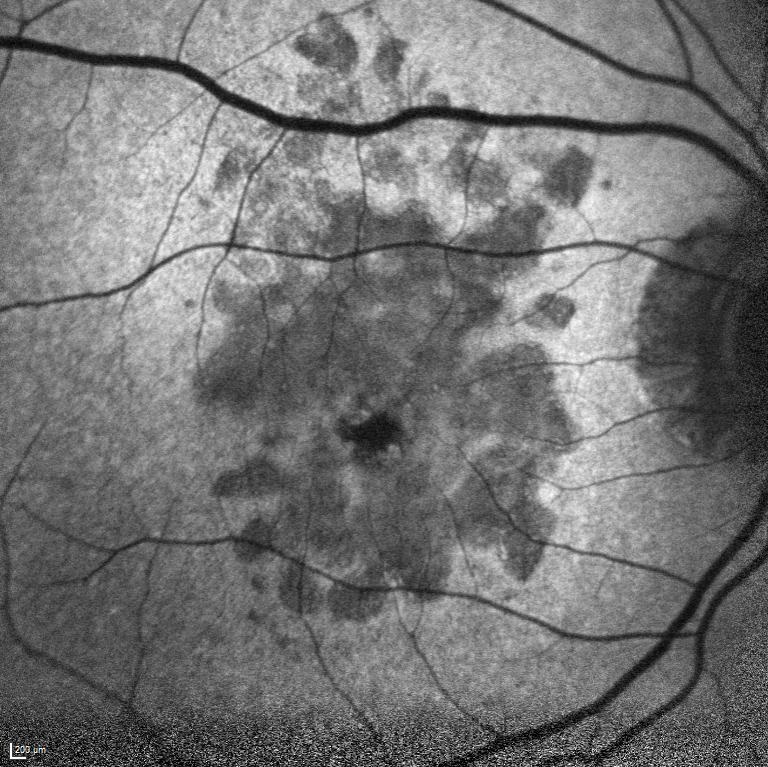

Her iki gözde doğuştan bu yana görme problemleri olan 11 yaşındaki erkek hastanı ...